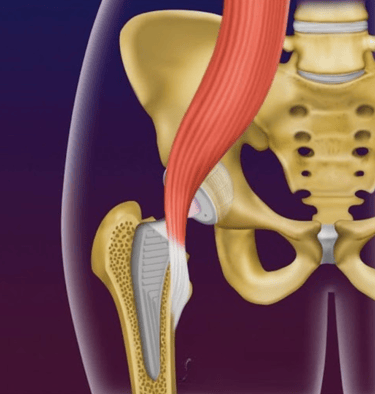

Tendinite de iliopsoas

É uma complicação infrequente, mas que causa dor na região da virilha após a colocação da prótese, principalmente ao se fazer flexão do quadril (movimento de puxar o quadril para cima).

Essa complicação pode ocorrer devido à proximidade do tendão do iliopsoas com a taça acetabular ou a cabeça da prótese, gerando um atrito constante entre o tendão e a prótese, levando à inflamação do tendão.

Imagem ilustrando o tendão do iliopsoas passando próximo à prótese de quadril, podendo causar tendinite do iliopsoas.

O tratamento é com repouso, medicações, Fisioterapia e possivelmente infiltração ao redor do tendão do iliopsoas.

Em casos que não melhoram com esse tratamento, podemos fazer uma liberação do tendão com artroscopia, procedimento simples e que melhora o quadro de dor e limitações.